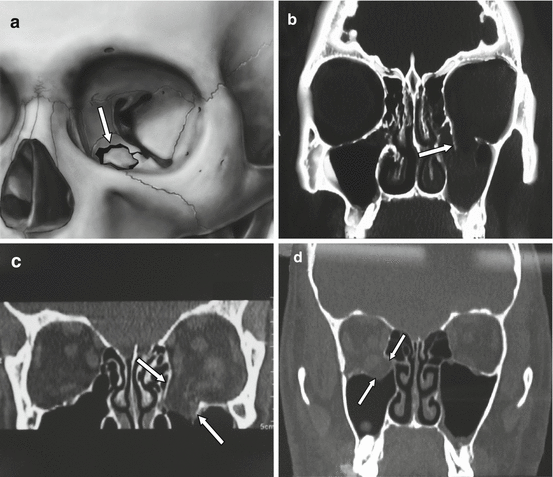

A Case Of Combined Orbital Floor And Medial Wall Fracture A 44 Year Old Download Scientific Diagram